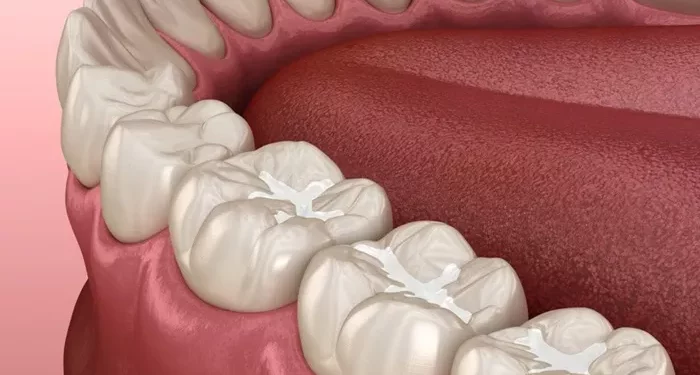

A cracked tooth refers to any damage to the tooth structure that leads to a visible break or crack in the enamel. Cracks can vary in size, from small, barely noticeable fissures to large, deep cracks that affect the entire tooth. Depending on the nature and extent of the crack, treatment may involve a variety of methods to restore the tooth’s functionality and appearance.

- Craze lines: These are small cracks that only affect the outer layer of the enamel and are usually harmless. Craze lines do not cause pain and often require no treatment.

- Fractured cusp: This type of crack occurs in the chewing surface of the tooth and typically involves the enamel. It may or may not be painful, depending on the depth of the fracture.

For minor cracks or chips in the tooth, dental bonding is often an effective and conservative solution. Bonding involves the use of a tooth-colored resin material that is applied to the cracked area. The dentist will shape the resin to match the natural contour of the tooth and then harden it with a special light.

Dental bonding is typically used for small cracks and is a quick and relatively inexpensive treatment. The procedure can usually be completed in a single visit, and the results can last for several years with proper care.